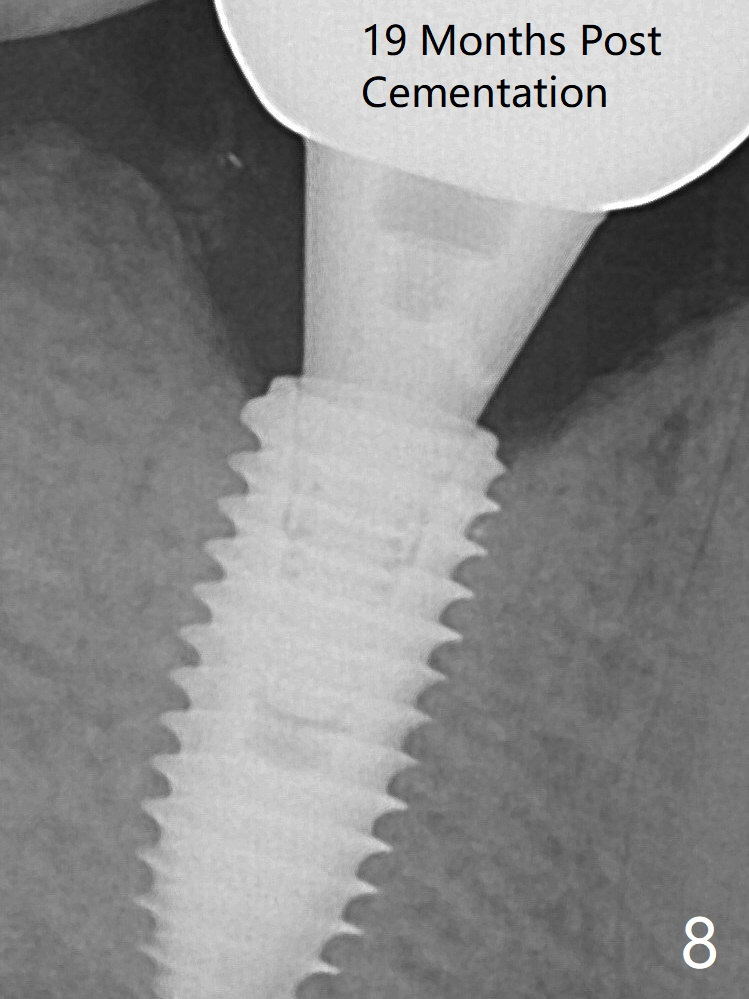

After insertion of a 5.7x5.5(3) mm abutment, Vanilla Graft is placed (Fig.5 * with 2 mm buccal gap). The abutment with a provisional is loose 4 months postop (Fig.6). The abutment screw is loose and fractured 8 and 11 months post cementation, respectively (Fig.7). The fractured screw seems to be loose within the implant well and is easily re-winded out. When the crown/abutment is loose 2nd time 1 year 7 months post cementation (Fig.8 taken post retightening), the screw at #19 fractures. The tooth #2 needs a crown. The patient cannot use the anterior teeth, since the teeth #8 and 9 have root fracture. Can extraction and bone graft increase bone height? The screw re-fractures 9 months later (Fig.9).